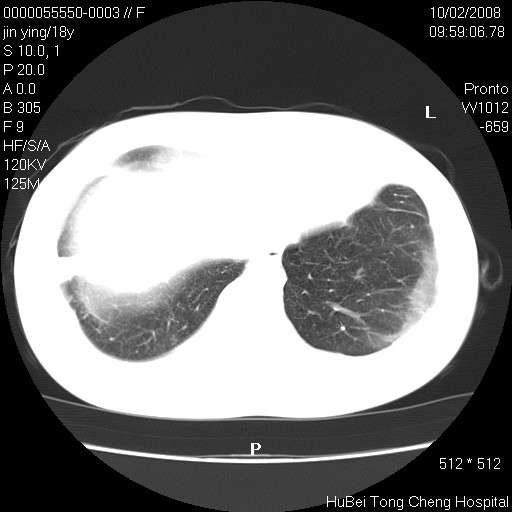

患者 女,18y。发热十余天,伴咳嗽。pe:t39⒈℃,bp 110/80mmhg,p 86次/min。神清,精神欠佳。双肺可闻及少许湿罗音。既往史不详。

临床诊断:肺部感染?

胸部ct轴位平扫(层厚10mm,螺距1.5,重建间隔10mm),图像如下: